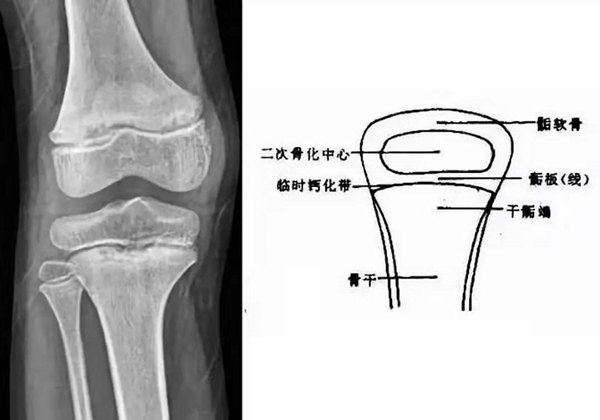

我們都知道,人體的高矮是由骨骼的生長(zhǎng)發(fā)育決定的,特別是下肢長(zhǎng)骨。長(zhǎng)骨呈長(zhǎng)管狀,在長(zhǎng)骨的兩端有一種專管骨骼生長(zhǎng)的骺軟骨,它與干骺端之間有一盤狀軟骨結(jié)構(gòu)稱為骺板(線),在幼兒的X光片上表現(xiàn)為一條較寬的透光帶。 (見下圖)

未成年時(shí)隨著年齡的增加骺軟骨端不斷骨化,骨骼就不斷增長(zhǎng)。當(dāng)骨骺線完全閉合時(shí)骨骼就停止生長(zhǎng),個(gè)子也就不再增長(zhǎng)了。一般骨骺端完全閉合的年齡是18~20歲左右。